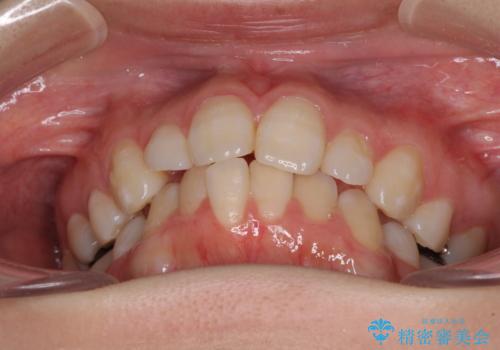

抜歯矯正の後戻り インビザライン・ライトによる矯正治療

- 矯正治療の後戻りを気にして来院された患者様です。

後戻りは軽微であったので、インビザライン・ライトにより矯正治療を行うこととしました。

治療途中、妊娠・出産があり、1年近く治療が停滞しましたが、無事に終了することができました。